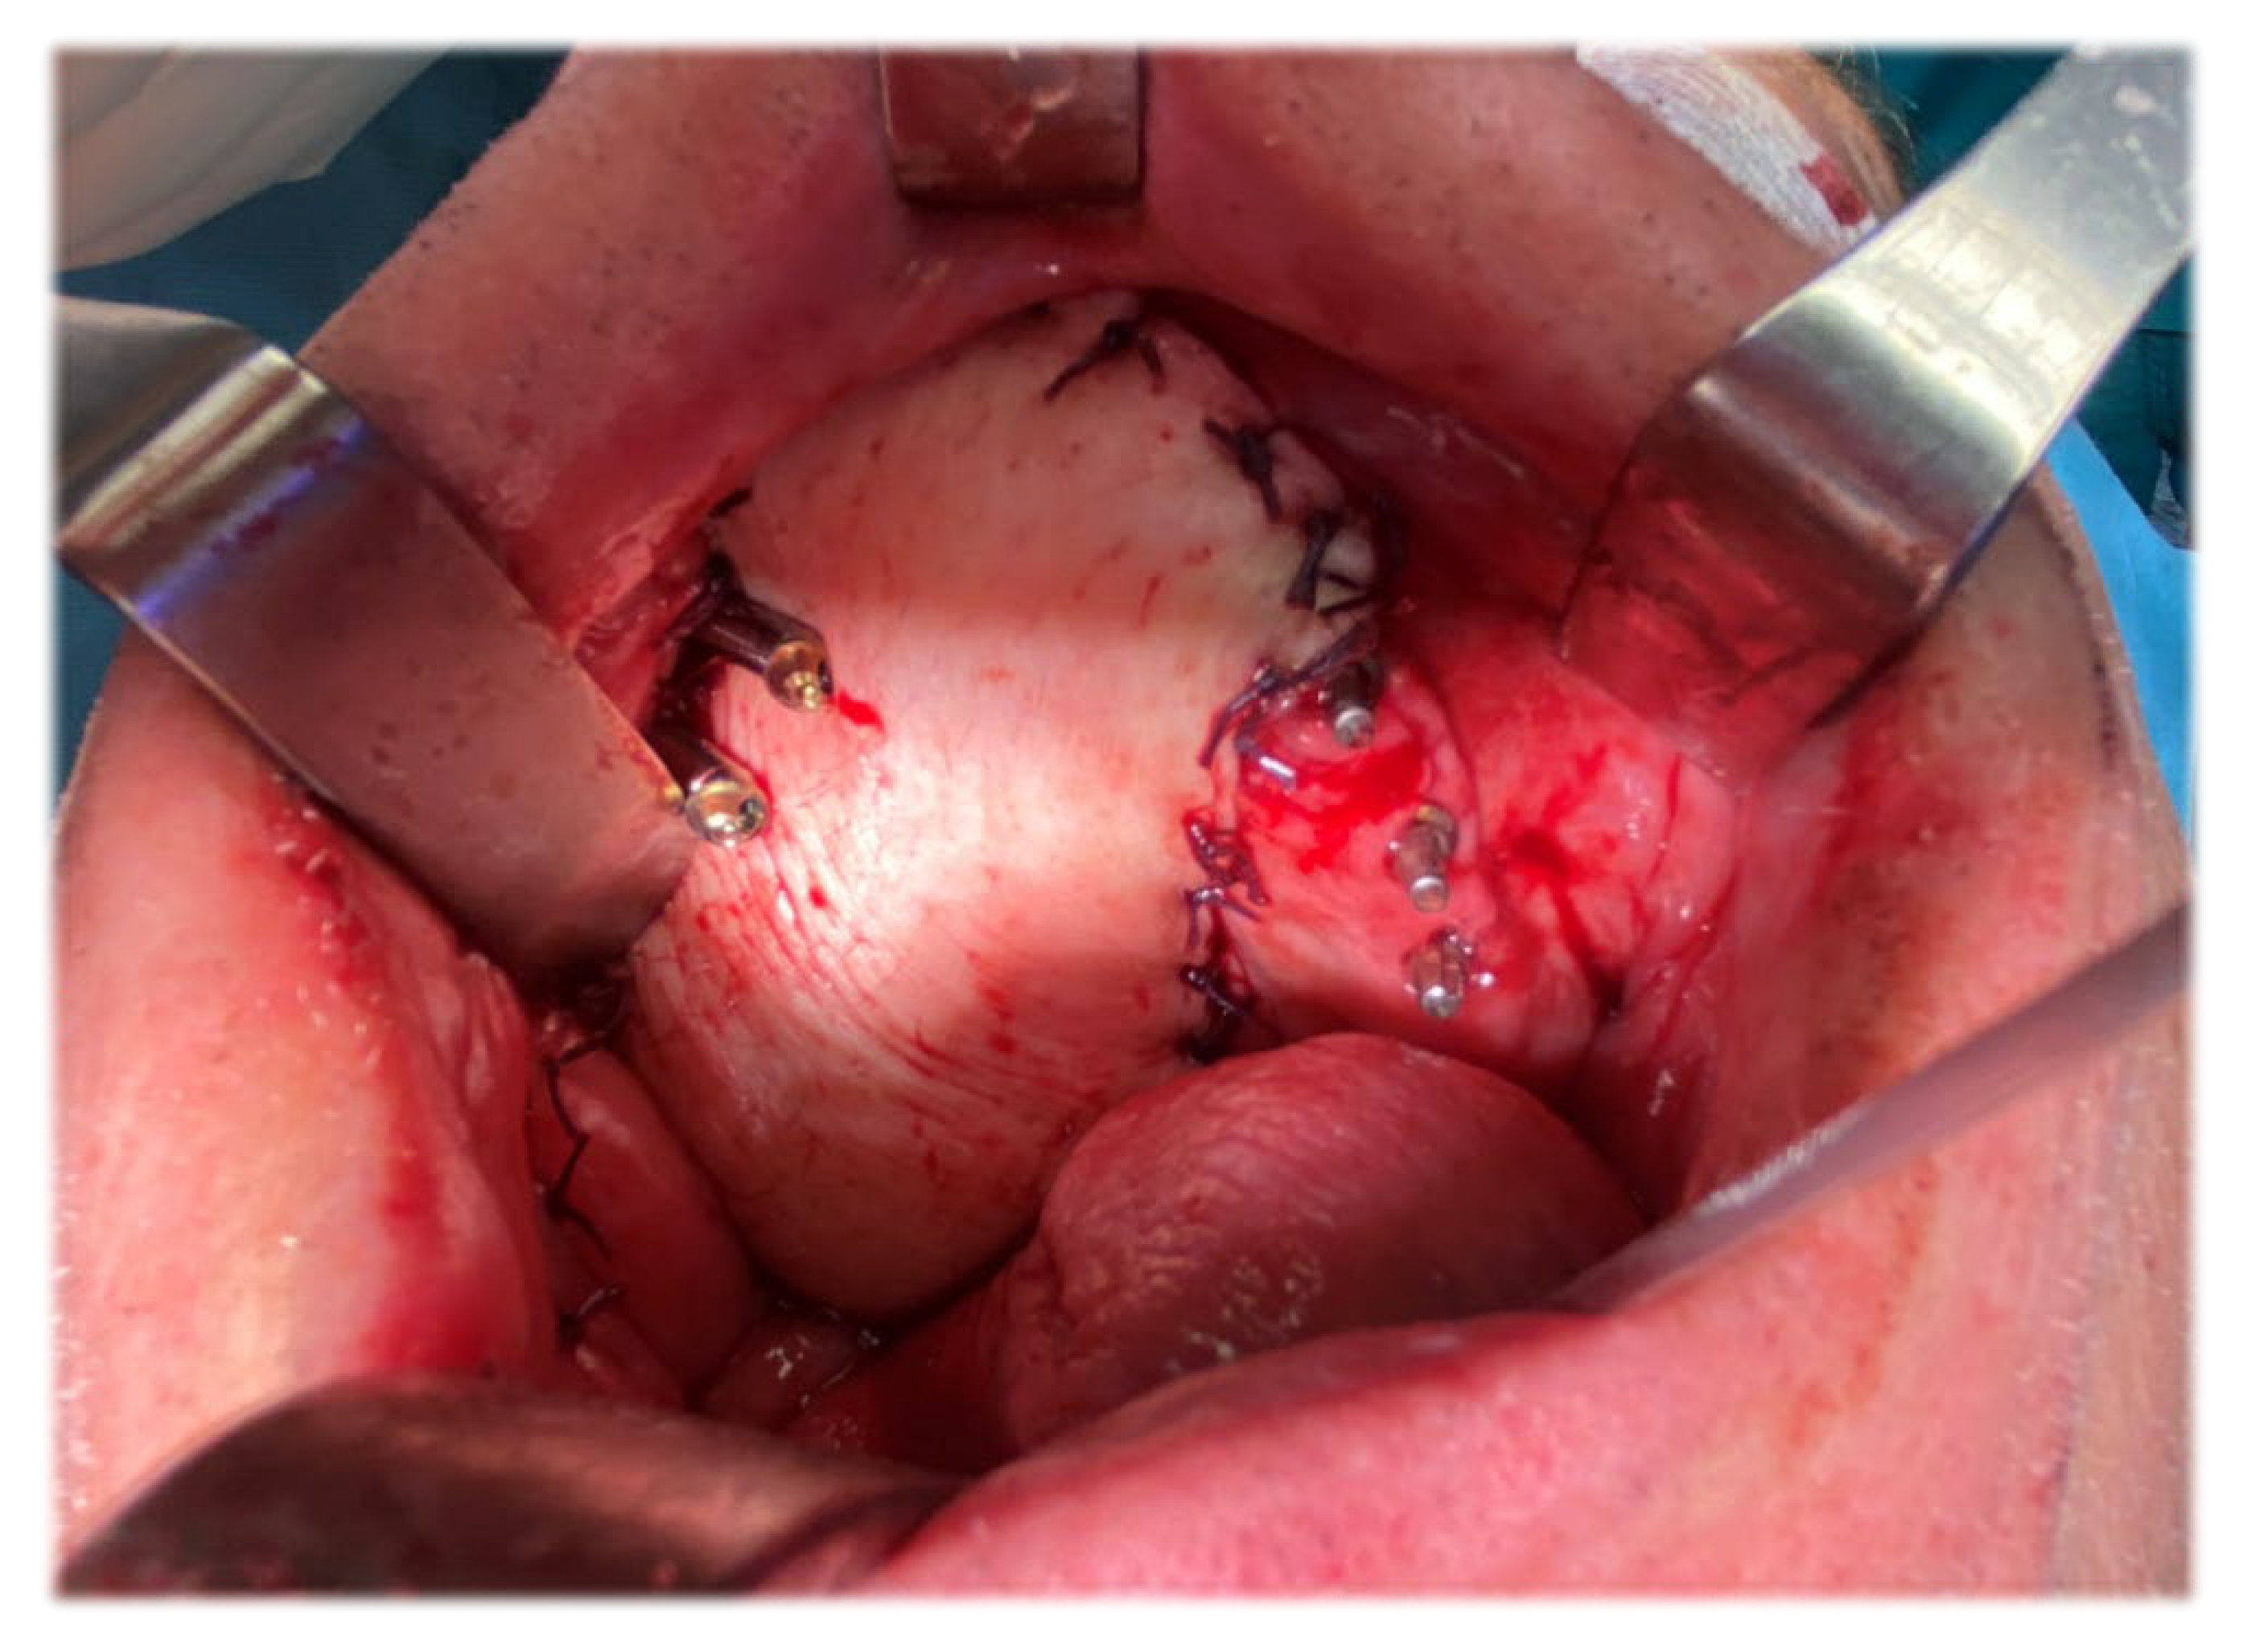

4. Surgical Technique

Post-Operative Report